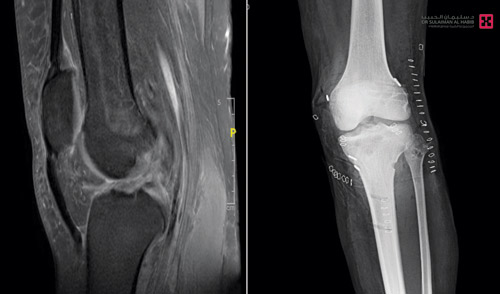

وأوضح د. حمدان أن الشاب كان قد تعرض قبل نحو «10» أشهر لحادث مروري مروّع، ولحقت به إصابات جسيمة بالركبة اليسرى، وبعد رحلة بحث طويلة غير موفقة راجع مستشفى الدكتور سليمان الحبيب مشتكياً من مجموعة من الأعراض الحادة تمثلت في الألم الشديد وعدم القدرة على مواصلة النشاط، وتورم بالمفصل مع فقدان لنطاق الحركة وشعور بعدم الثبات أو «الانهيار» عند محاولة تحمل الوزن، إضافة إلى مشكلة في ثني الركبة ينتج عنها صعوبة بالمشي. وأضاف د. علاء أن نتائج الفحوصات أظهرت أنه مصاب بقطع في ثلاثة أربطة للركبة «المتصالب الأمامي، والمتصالب الخلفي والرباط الجانبي الخارجي»، بالإضافة إلى ضغط شديد في العصب المغذي للعضلات الباسطة للقدم. وتم إجراء عملية منظار متقدمة للمريض لإعادة الثبات للركبة بزراعة الأربطة الـ«3» المتضررة بالقطع، وتحرير العصب المغذي للقدم اليسرى، وتكللت العملية ولله الحمد بالنجاح التام، وغادر المستشفى بحالة صحية جيدة، وتشير كل المعطيات الطبية إلى أنه سيستعيد قدرته الطبيعية على الحركة والمشي على قدميه بعد استكمال علاجه في وحدة العلاج الطبيعي.